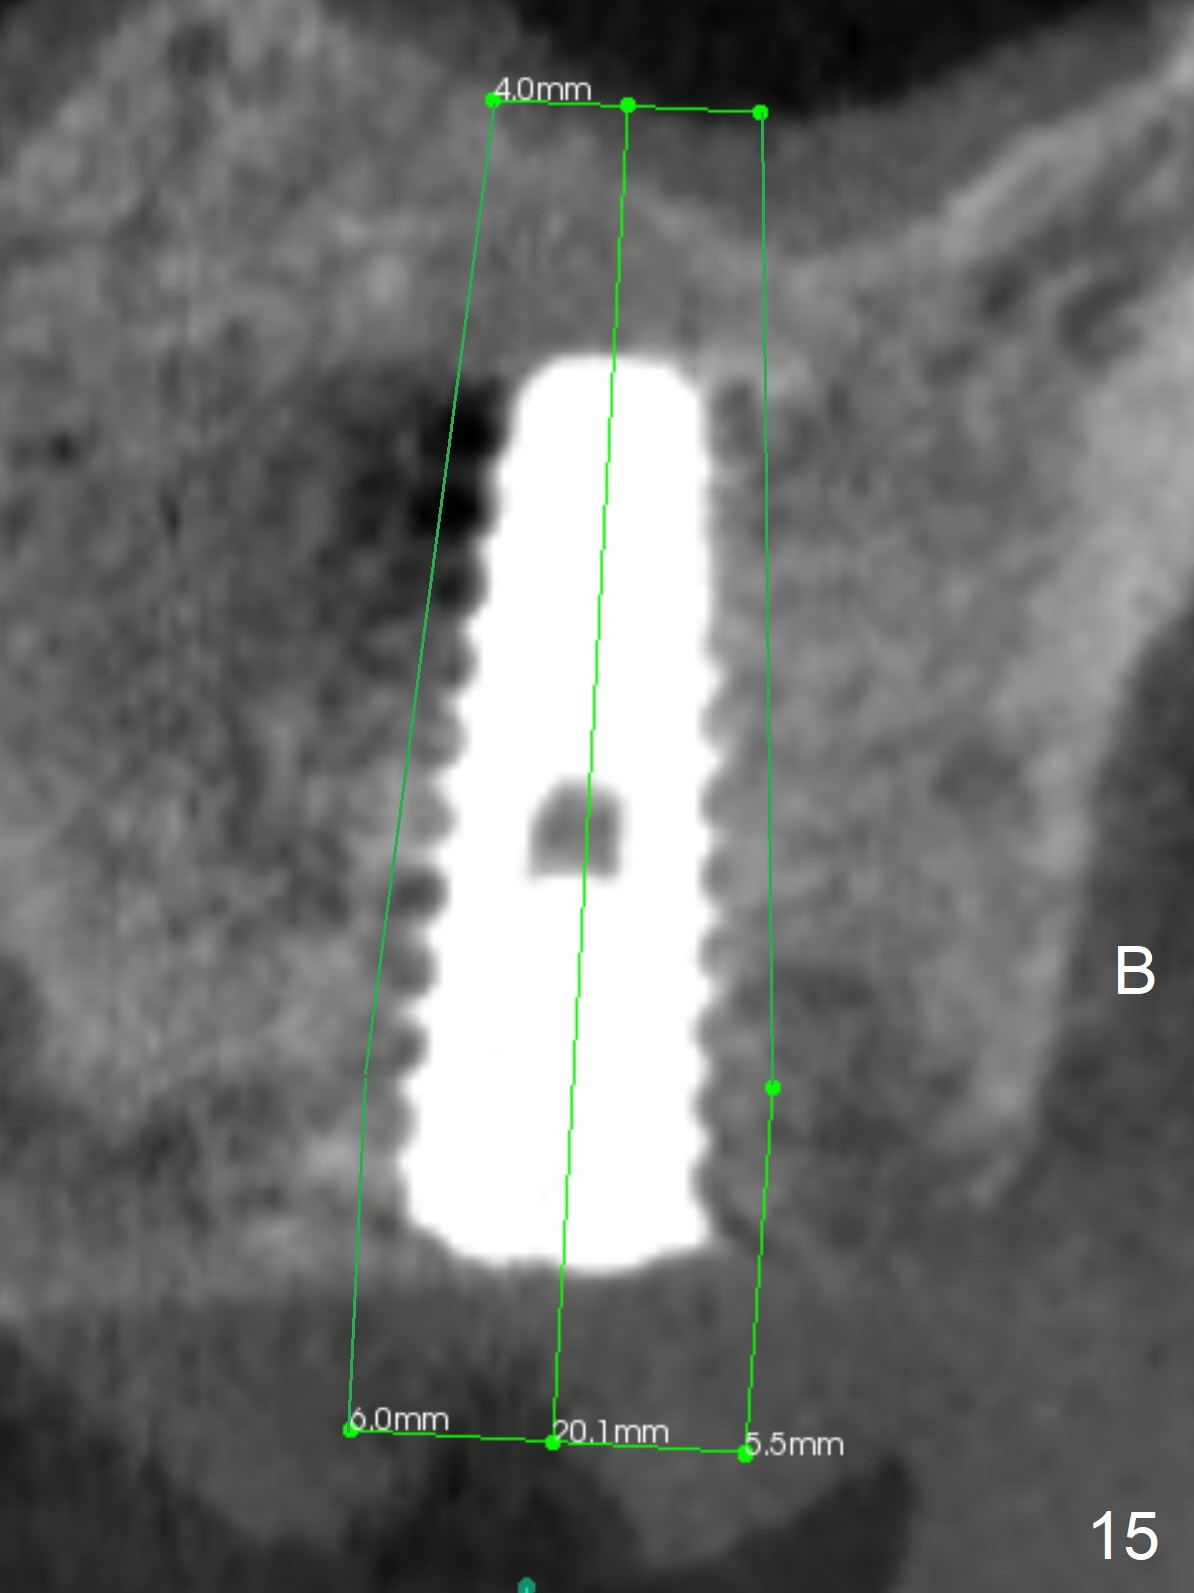

The amount of the bone graft mesial and distal the implant seems to reduce 3 and 4 months postop, respectively (Fig.6,7 arrowheads). When the acrylic is cut off 4 months postop, the bone graft is loose. The gingiva is unhealthy. The abutment and implant are loose. A healing abutment is placed (5x4 mm). The implant is torqued to 35 Ncm 6 months postop with the healing abutment reapplied. The patient will return for follow up nearly 9 months postop. A larger healing abutment will be used if the implant is stable. Two weeks later, use a smaller restorative abutment for easy impression. In fact the implant is unstable with #15 mesial shift due to abnormal occlusion with #17 (Fig.8). Bone density around the implant is low (* in Fig.9 (PA), 10,11 (CT sagittal, coronal sections)). A healing screw is placed for self healing. A 2nd option is to remove the implant (Fig.12), BEB (Fig.13) and place the implant deeper (Fig.14) or larger one (5.5-6.5x13 mm). The 3rd option is to place larger and longer implants (Fig.15 (tapered), 16 (cylindrical)). The implant access has partially closed 14 months postop, but there is a small buccal opening with sanguine exudate. Incision reveals severe bone loss around the implant; the mobile tooth #15 is extracted (Fig.17). After debridement and irrigation with normal saline, Vera Graft (Fig.18 *) and Collagen plug are placed with periodontal dressing.